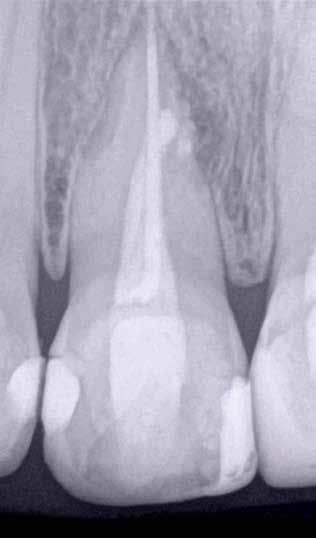

ai felvételek segítségével viszonylag jól el lehet különíteni a külső rezopció okozta ártalmaktól. A belső rezorpciótól szenvedő fogak esetében a radiológiai felvételek excentrikus irányból történő elkészítése során a rezorptív lézió a fog gyökércsatornájával egy irányba mozdul el a felvételen, míg külső rezorpció esetében le fog vetülni a gyökércsatornáról. 1999 márciusában egy 47 éves hölgy páciens arcduzzanattal kereste fel a rendelőnket. Klinikai vizsgálat során a jobb felső nagymetszőfog (11) kopogtatásra való érzékenységét tapasztaltuk. A felső front régióról készült periapikális felvételeken a frontfogakban lévő nagy kiterjedésű III. és IV. osztályú restaurátumokat észleltünk. Az 11-es fog gyökércsúcsa körül periapikális felritkulás volt látható. A 21-es fognál a gyökér középső harmadában belső rezorpciót észleltünk (13. ábra). A páciens kérdésünkre elmondta, hogy a bal felső nagymetszője közel 35 évvel ezelőtt traumás sérülést szenvedett. Mivel abban az időben CBCT-felvételek készítése nem volt számunkra elérhető, így a klinikai adatok alapján azt feltételeztük, hogy a rezorptív lézió bukkális irányba perforálta a gyökércsatorna falát, majd ezt követően az ezt a területet fedő bukkális csontállományt is destruálta.

A frontrégióban végzett szenzibilitás vizsgálat is megerősítette a 11 fogban a fogbélelhalás diagnózisát. Az 11-es fog endodonciai kezelése során a gyökércsatorna biokemo-mechanikai megmunkálását követően a gyökércsatornát meleg vertikális kondenzációs technikával zártuk. A bal felső nagymetsző esetében a gyökércsatorna megmunkálását a rezorpciós üreg koronális határáig végeztük, majd a megmunkált csatornaszakaszt fehér MTA-val töltöttük fel (14. ábra). Amennyiben ennek a fognak a kezelését ma kellene elvégezni, akkor az EndoSequence BC puttyt (Brasseler) használnánk a gyökértömés elkészítésére. Ezenkívül azt is megemlítenénk, hogy manapság egyre gyakrabban próbál-

13. ábra: A periapikális felvételen jól lekövethető a 11-es fog gyökércsúcsa körül látható radiolucens terület körvonala. A 21-es fog gyökerének középső harmadában pedig belső rezorpció jelenlétére utaló jelek észlelhetőek. A rezorptív lézió frontális és laterális irányban is áttörte a csontos falakat, amely következtében a gyökeret körülvevő csontállomány is károsodott. – 14. ábra: A posztoperatív felvételen jól megfigyelhető a 11-es fogba helyezett gyökértömés. A 21-es fog ellátása során a gyökércsatorna megmunkálását csak a rezorptív defektus koronális határáig végeztük. A gyökércsatorna zárására fehér MTA-t alkalmaztunk. – 15. ábra: A 11-es fog gyökércsúcsa körül látható felritkulás teljesen eltűnt. A rezorptív defektus mérete csökkent, valamint a rezorpciós üreg csontosodására utaló jelek is megfigyelhetőek. – 16. ábra: A saggitalis irányú CBCT-metszeten jól látható, hogy a 21-es fogat ép és jól megtartott bukkális kortikális csont fedi. A rezorpciós üreg mérete jelentősen csökkent, valamint az üreg kalcifikálódott anyaggal való telődése is megfigyelhető volt.